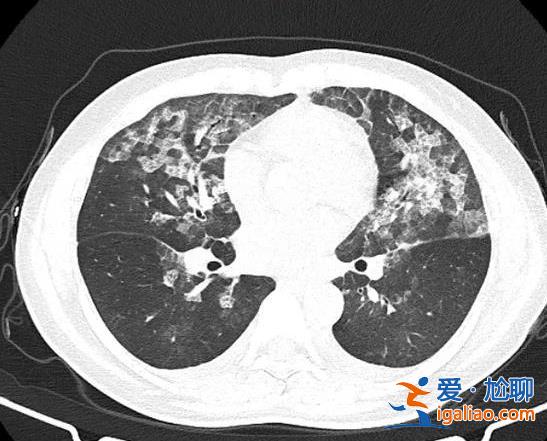

官方解答白肺現(xiàn)象?

什么是白肺?白肺是醫(yī)學(xué)上對肺部影像的通俗描述。當(dāng)肺泡發(fā)生炎癥和感染,有滲出液和炎性細胞時,肺泡內(nèi)就充滿了這些滲出液或炎性細胞,使射線穿透時無法穿透。...